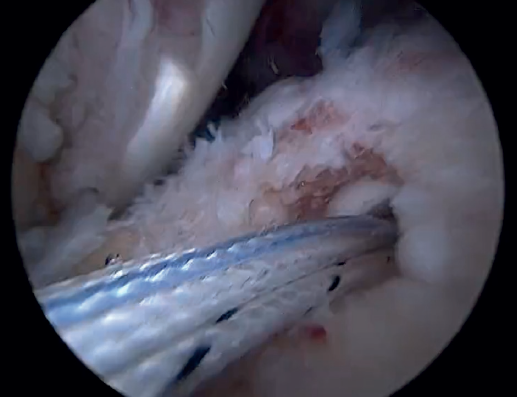

Tension-free repair of the supraspinatus tendon is then made, using the free thread left at the anchoring and taking advantage of the two sutures passed through and knotted to the proximal LPB fragment (Figures 8, 9 and 10).

The free suture remaining at the anchoring is passed through the anterolateral supraspinatus using a Scorpion® direct suture passer (Arthrex, Naples, FL, USA), as a sliding mattress suture over the implant.

One end of each of the sutures exiting the LPB is passed through the supraspinatus likewise using a Scorpion® direct suture passer (Arthrex, Naples, FL, USA). All the threads are left unknotted and are recovered through the anterior working portal so that they do not get in the way when working later on. Note that the two threads exiting the LPB and passing through the supraspinatus will not slide; it is therefore advisable to knot them and lower them later on with a knot pusher. This point allows repair of the anterior supraspinatus to be combined with fixation of the LPB in the anterolateral zone of the greater tuberosity.